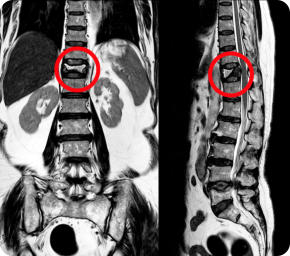

A senior man stands straight holding a box of plants wearing gardening boots and a straw hat X-ray of a spine with a fracture. The fracture is circled in red.

X-ray of a spine with a fracture. The fracture is circled in red.